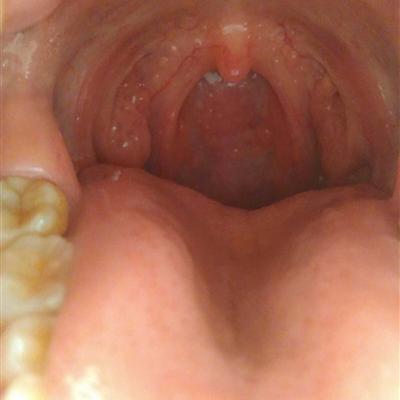

The incidence rate of halitosis is very high in life. The bad breath is not the cause of not brushing one's teeth for a long time. No matter what kind of disease it is, it must be treated in a timely manner. It is mainly the result of cold drinks and stomach function being trapped by cold evil, and Yang Ming and dryness heat. For example, if a person in a normal state is suddenly immersed in ice water, the propaganda function of the fur will be trapped, and people will use the form of fever to drive away the cold evil, so the symptoms of fever will appear. How about baby halitosis?? Do you know? Today, let me learn from you about baby halitosis?.

First: the baby's bad breath may be caused by insufficient drinking water, dry mouth is the most direct cause of bad breath. When the mouth is dry, the anaerobic environment in the mouth is very suitable for the breeding and overgrowth of these anaerobic bacteria, and it will decompose to produce sulfide and give off the smell of corruption, which is the root cause of halitosis. Most people fall asleep at night, due to the reduced function of the mouth, saliva secretion is reduced, which is very conducive to the breeding of anaerobic bacteria, therefore, in the morning there will be bad breath. Similarly, the decrease of salivary gland function in the elderly and the decrease of salivary secretion caused by endocrine disorder in women during menstruation are the causes of halitosis in these two groups

Second: poor oral hygiene often leads to dental plaque accumulation on the surface of teeth and the junction between gums and teeth. "Dental plaque is the main cause of dental caries and periodontal disease, and it is also one of the causes of halitosis, because the place where dental plaque accumulation may be a good place for anaerobic bacteria to survive, and it is also the direct cause of halitosis.